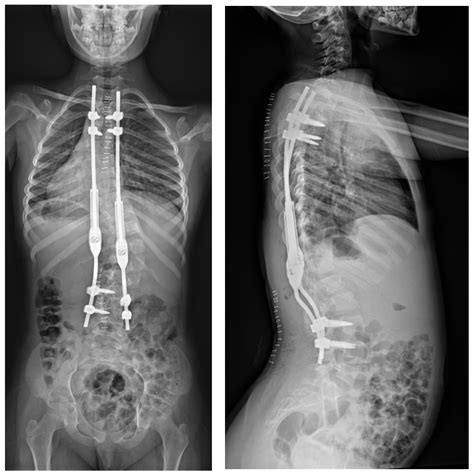

Growing Rods Surgery Is Helping Children With Scoliosis Thrive

Understanding Scoliosis Surgery – ScoliCare